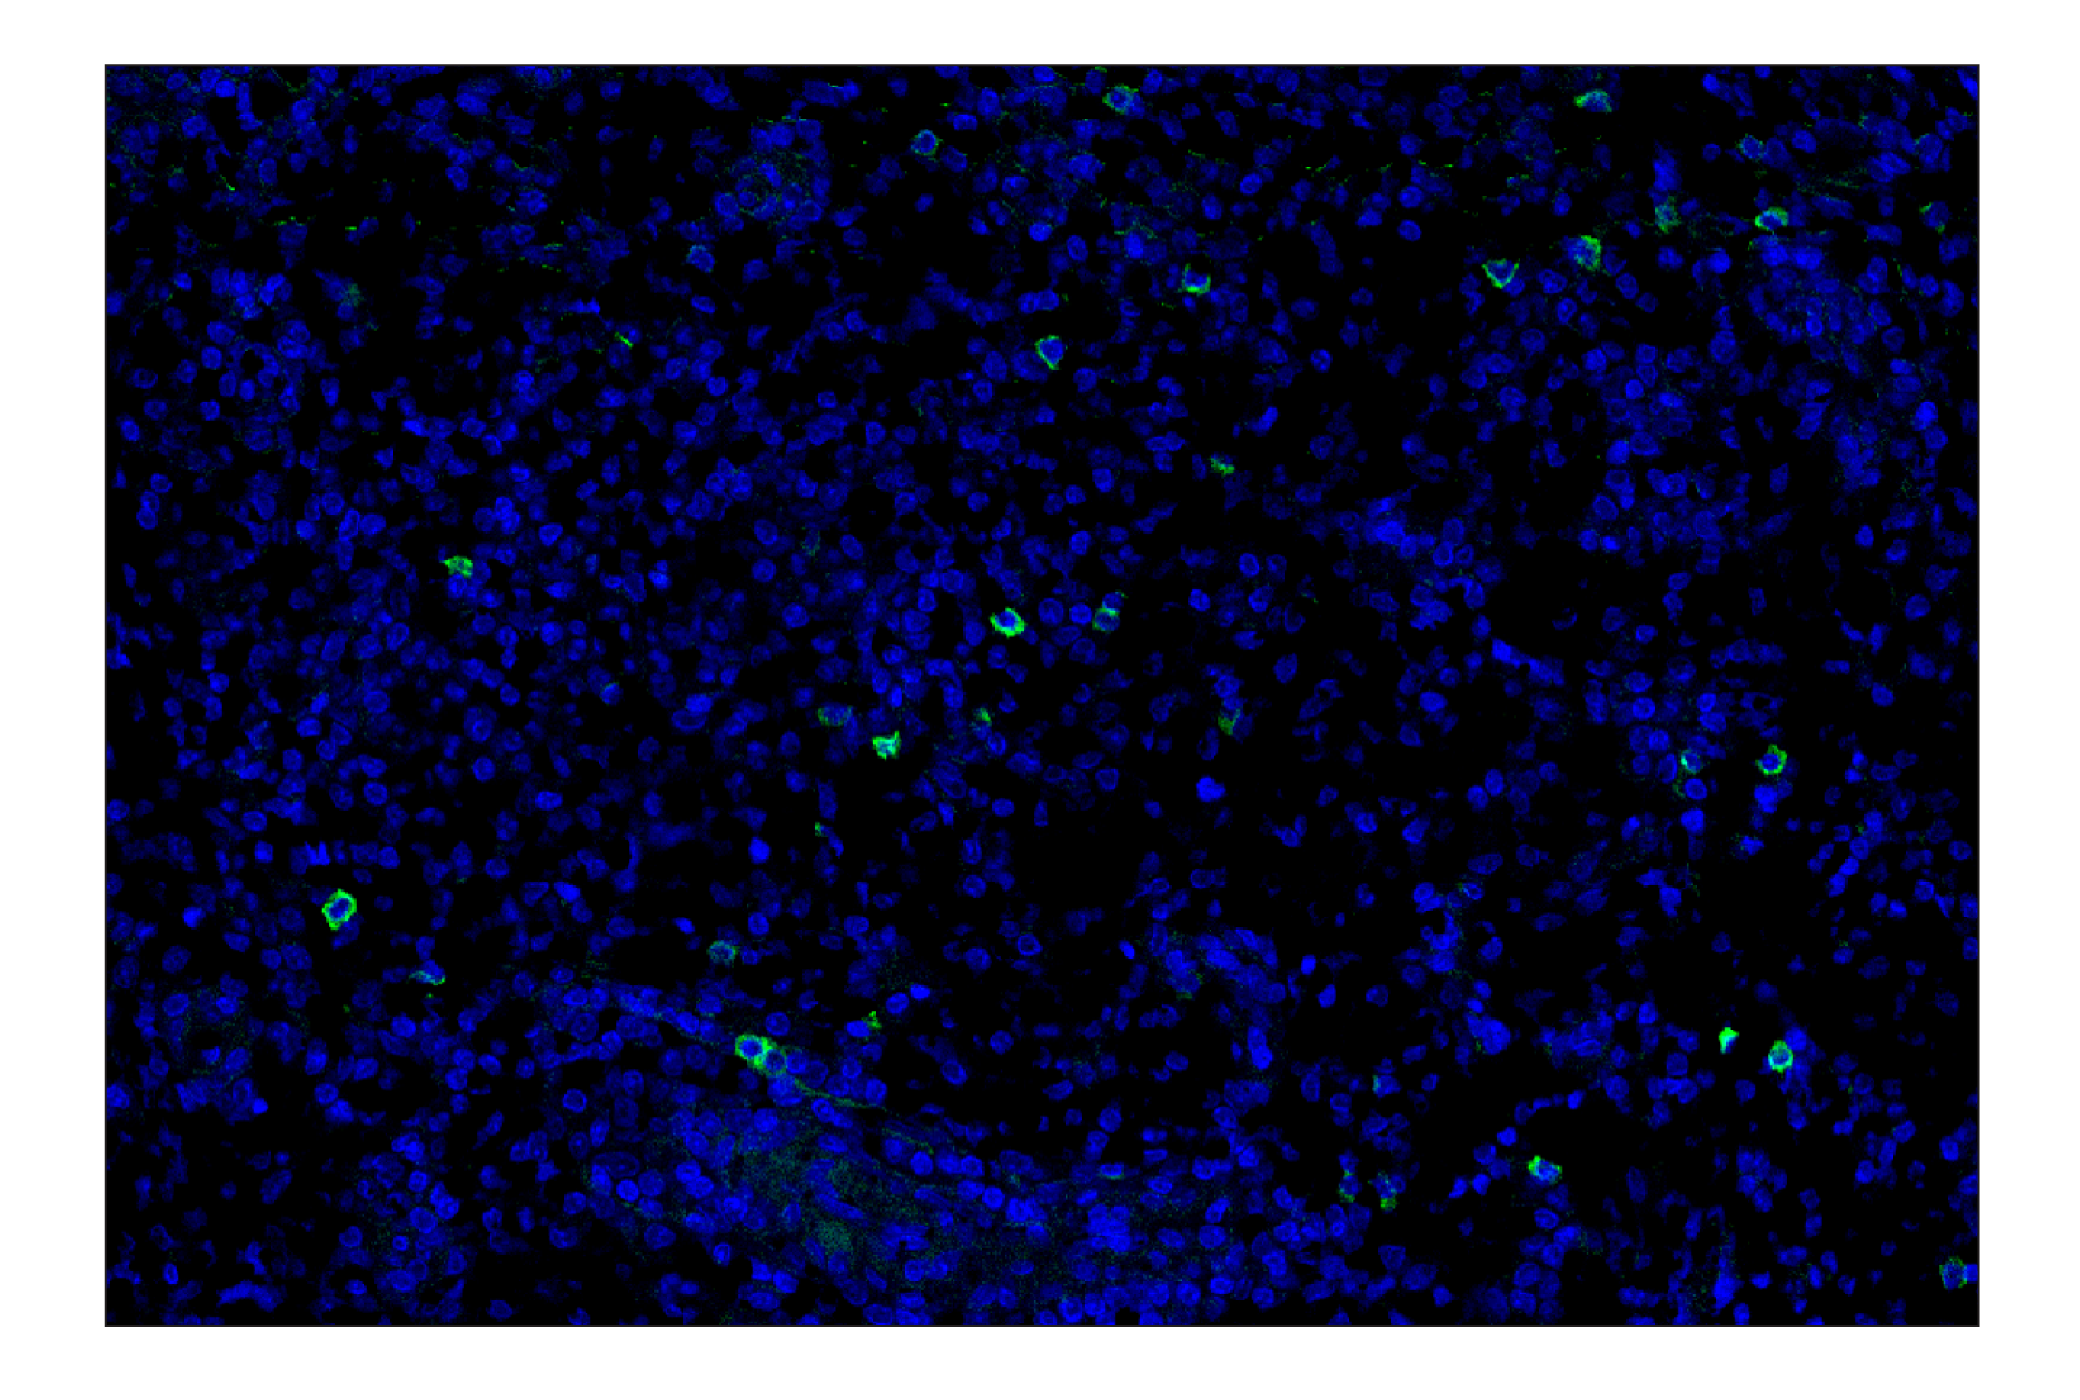

TRDC/TCR delta (E2E9T) Rabbit Monoclonal Antibody (Alexa Fluor® 488 Conjugate) #33883

Immunohistochemistry (Paraffin) 1:50 - 1:200

TRDC/TCR delta (E2E9T) Rabbit Monoclonal Antibody (Alexa Fluor® 488 Conjugate) recognizes endogenous levels of total TRDC/TCRδ protein. This antibody does not cross-react with human TRAC/TCRα constant, TRBC1/TCRβ constant region 1, TRBC2/TCRβ constant region 2, or TRGC1/TCRγ constant region 1.